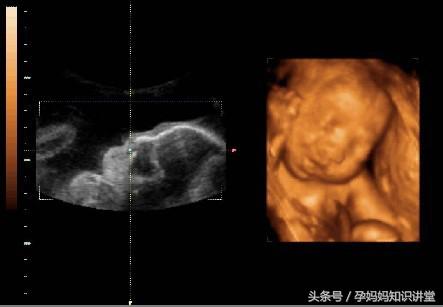

一、胎儿状况

1、体重:怀孕36周,孕妈的体重已经达到了最高峰,胎宝宝的身体发育已经基本完成了,体重已经有2.8千克了。

2、四肢:胎儿的四肢会在子宫里自由地活动,并且手指还能轻轻地碰到嘴唇,完成吮吸的动作。

3、骨骼:胎宝宝的骨骼基本发育成熟,已经相当的坚硬了。但是头盖骨的形状还不固定,在分娩的时候,为了顺利通过妈妈的产道,宝宝的头骨会发生变形,到产后几个月慢慢地孤星形状。

4、胎位:可能有些胎儿已经完成了入盆,将自己头部埋在妈妈的盆骨处,背部朝向妈妈的子宫,做出跃跃欲试的姿势,随时准备和妈妈见面。